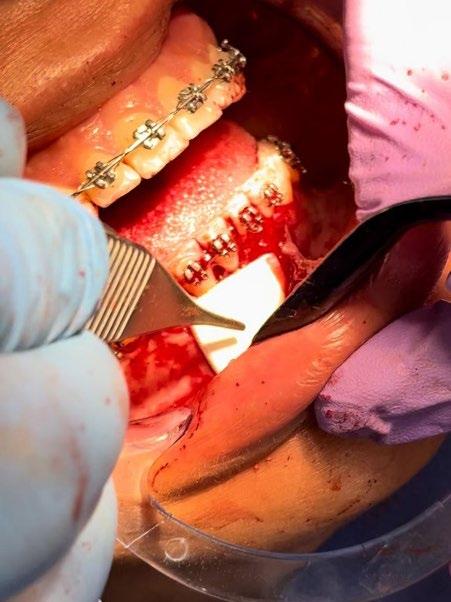

Se presenta un paciente de 18 años de edad que refiere tener hemofilia tipo A, moderado grado V. En los estudios de inicio extraorales, se observa en la Figura 1 el frente, sonrisa y perfil. En la radiografía lateral de inicio (Figura 2) se evidencian el overjet y overbite reducidos, clase I esquelética, hiperdivergencia y biprotrusión dentoalveolar.

El tratamiento se realizó en las siguientes fases: la fase prequirúrgica incluyó la alineación, nivelación y la

extracción de los segundos premolares superiores e inferiores, con cierre de espacios. En la fase quirúrgica, se realizó una mentoplastia de avance e implantes en la zona malar. La fase postquirúrgica consistió en el detallado-retención. La aparatología utilizada fueron brackets de prescripción Roth .022 × .028; se colocaron bandas en los primeros molares superiores e inferiores, con tubos punteables en los O.D. 16, 26, 36 y 46, y tubos bondeables en el O.D. 27, además de un arco transpalatino y un arco lingual.

desviadas. En las Figuras 4, 5 y 6 se observa la forma de las arcadas superior e inferior.